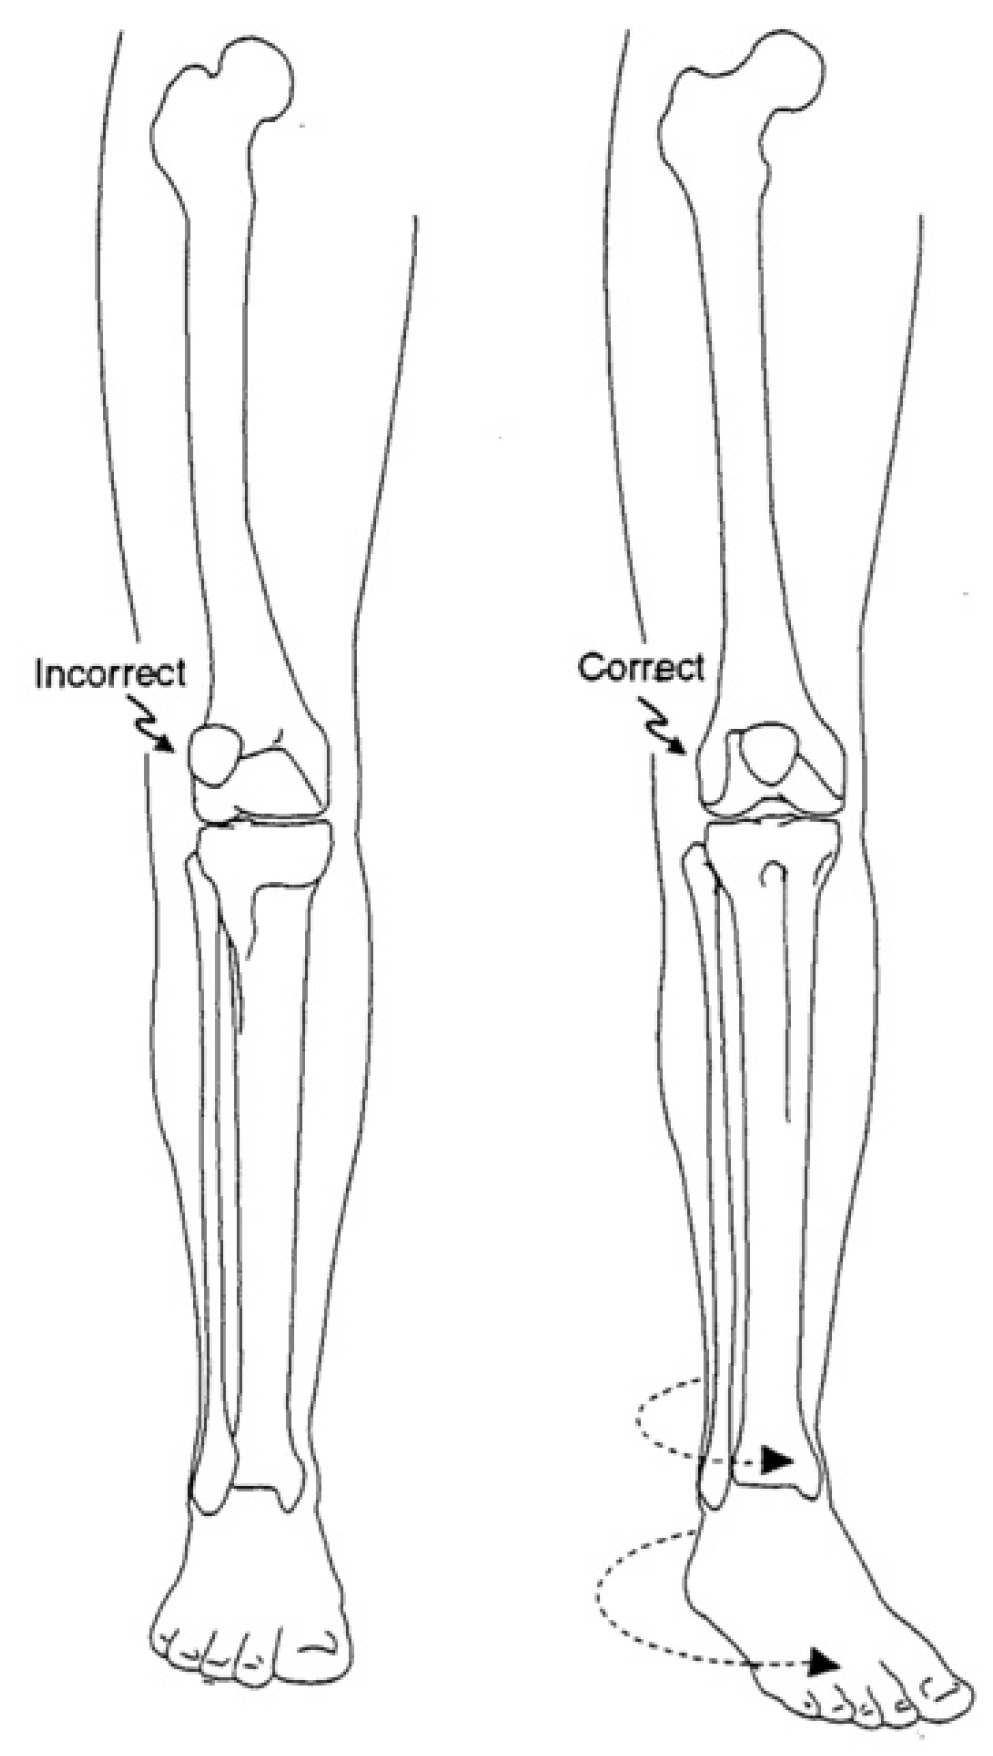

12. Physeal Arrest Resection

13. Osteotomies with Acute Correction